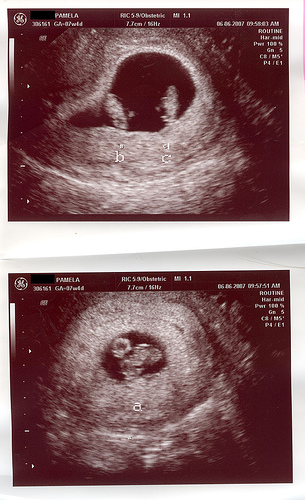

Уже на первой неделе задержки менструации беременность может быть видна в маточной полости в виде маленького пузырька жидкости. Следующим появляется плодное яйцо, которое видится в маточной полости тёмным чётким кружком, окруженным в качестве надежного признака более светлой зоной. Это указывает на наличие зачатка плаценты. Затем внутри плодового яйца будет виден желточный мешок, в котором формируется первичное кровообращение плода.

Обычно плод будет виден по завершении 5-ой недели беременности. Начиная с этого срока также можно измерять длину плода. Сердечная деятельность плода будет видна с 6-ой недели беременности и это подтверждает благоприятное протекание беременности.

Наступает период быстрого роста плода. Он растет 1 мм в сутки. Лучшее время для первичного ультразвукового исследования при беременности — 7-ая неделя беременности, когда длина плода составляет 10 мм и его сердечная деятельность отчётливо видна. На этой стадии беременности частота сердцебиения плода составляет более 110 раз в минуту.

- При нормальном течении на 6-7 недели беременности на УЗИ плод становится видимым и регистрируется сердцебиение, которое врач дает послушать при желании.